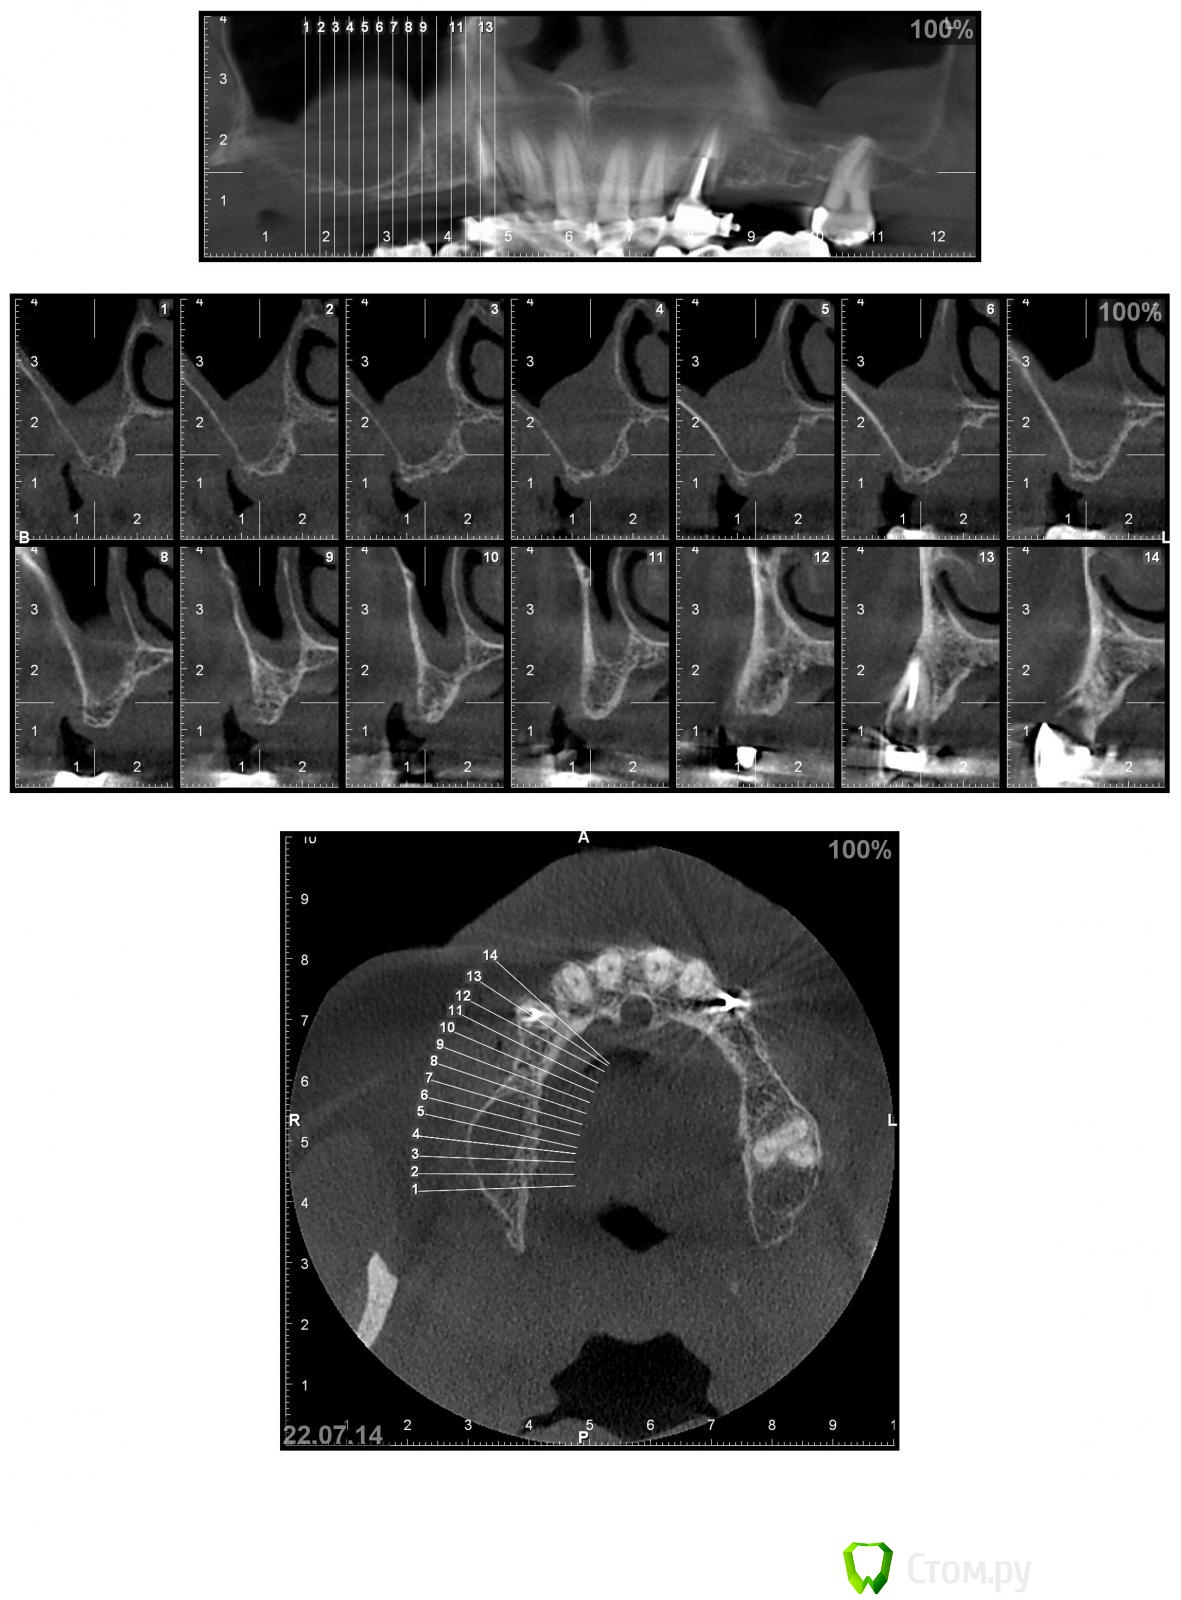

Nadeghda Опубликовано 13 октября, 2014 Поделиться Опубликовано 13 октября, 2014 Доброго времени суток, коллеги!Хотела узнать мнения относительно вариантов протезирования в/ч пациента.После консультации ЛОР - врача от оперативных вмешательств на ППН отказался. 13 и 23 удалены, лунки затягиваются. Варианты:1) имплантаты 13,15,23,25- мостовидные конструкции2) имплантаты 13.23; 15 и 25 - под углом 35'(ski)- локаторы- съемный протез3) имплантаты 13,23; 15,25- под углом 35' - мостовидные протезыМожет еще кто-нибудь что-либо предложит?Заранее спасибо! Ссылка на комментарий